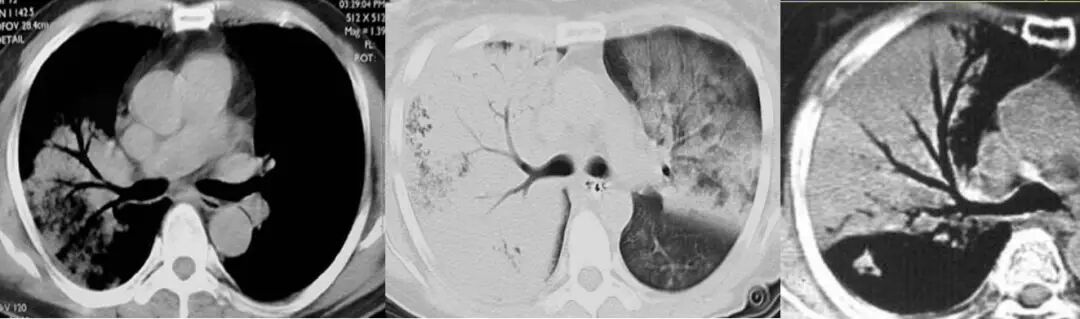

MALT 的支气管扩张并无支气管管壁的破坏。由于淋巴瘤组织浸润导致肺泡塌陷,支气管周围实质破坏造成的,这类支气管扩张在肿瘤治疗后有时可消失。

大叶性肺炎

临床症状:高热,咳嗽,咳铁锈色痰;

白细胞总数及中性粒细胞增高 ;

肺段/肺叶分布,片状实变影;

充气的支气管管径、形态均正常。

肺粘膜相关淋巴瘤

结节、肿块,边缘模糊

充气支气管粗大、扭曲